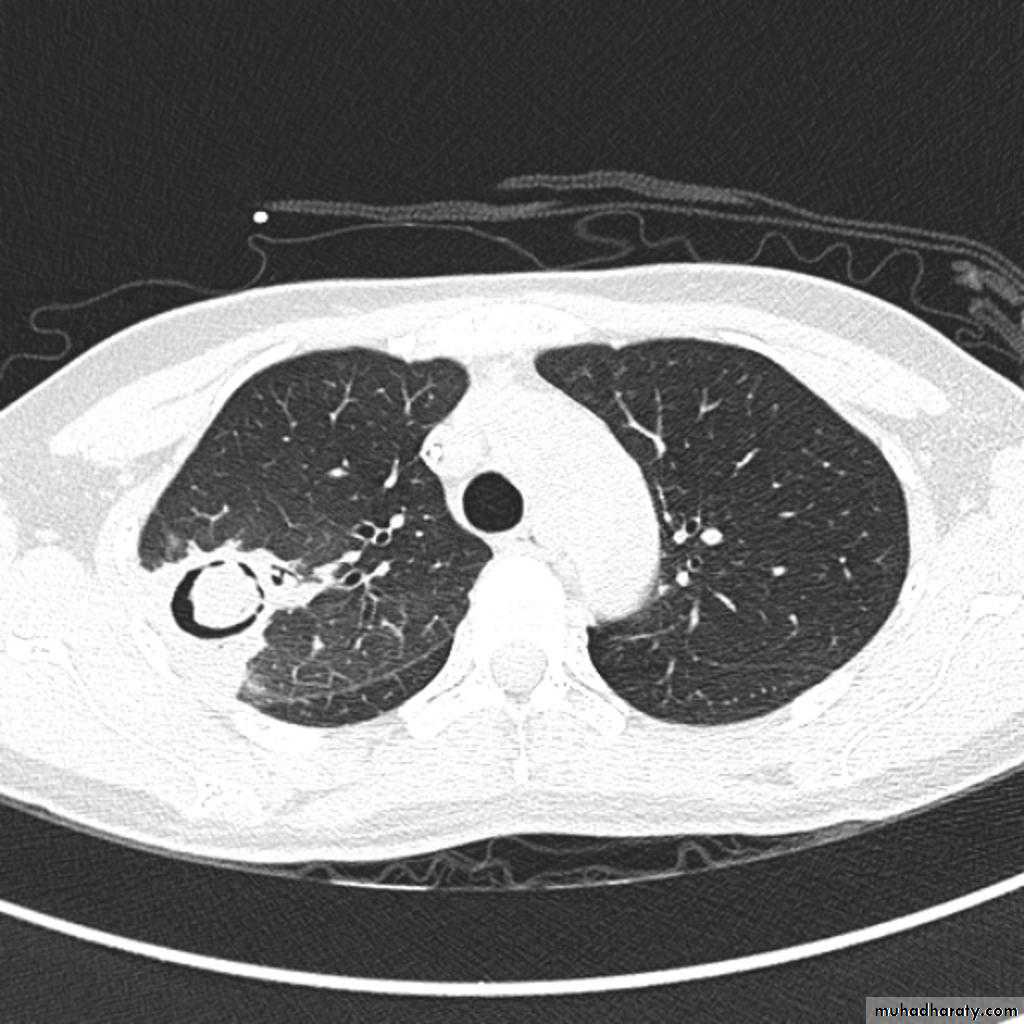

TB lung abscess

67.upper apical TB cavity68.Aspergilloma